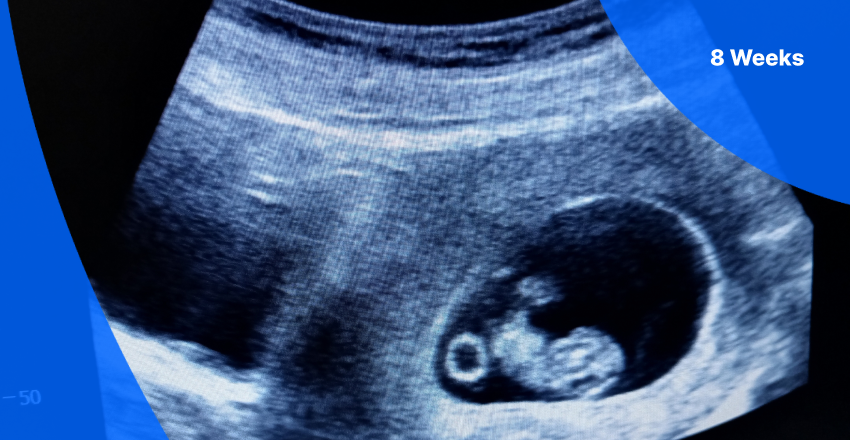

La 13 zile dupa transfer, femeia a avut primul test de sarcina pozitiv, care a progresat pana la o sarcina clinica confirmata. La 8 saptamani de gestatie, pacienta a trecut la ingrijire obstetrica, ecografia aratand o dezvoltare fetala normala si o frecventa cardiaca de 172 de batai pe minut.

Sursa foto: PocketHealth